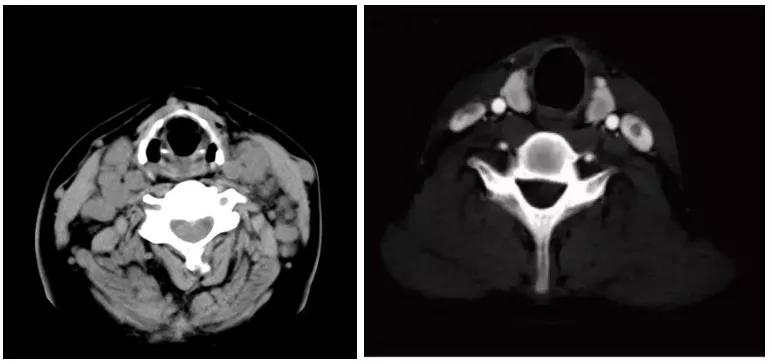

治疗1个月后,Zach甲状腺肿瘤完全消失,颈部超声检查证实了癌性淋巴结已越来越小,血流量也越来越少,这表明该淋巴结很可能最终将消失。

治疗前后甲状腺超声对比图